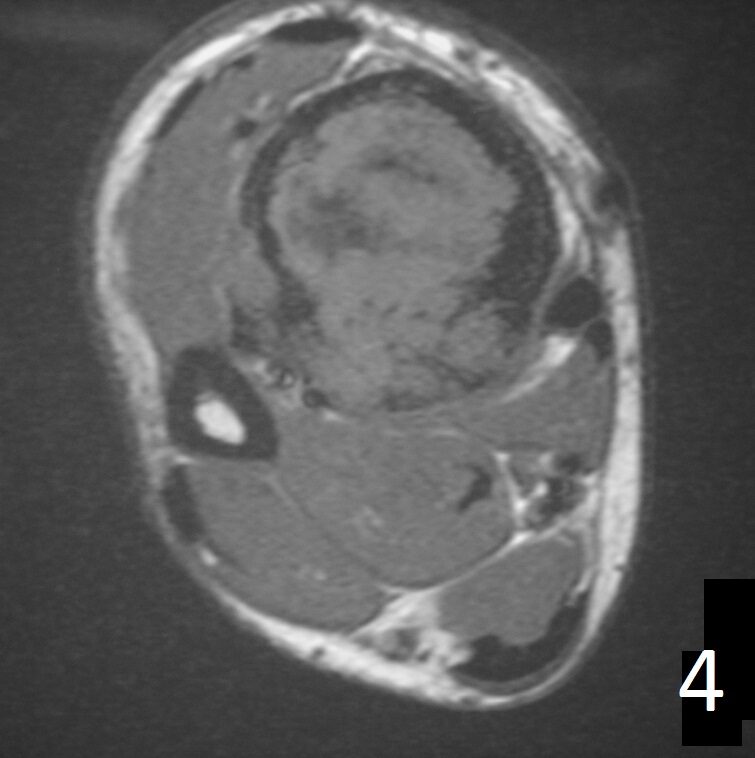

MRI (Fig. 4-5)

• Ideal to describe soft tissue involvement

• Sequences often follow that of fibrous tissue with low signal on T1 weighted and T 2 weighted images

Fig. 4

Fig. 4-5: Axial MRI of leg demonstrates a tibia lesion with cortical destruction and soft tissue involvement.